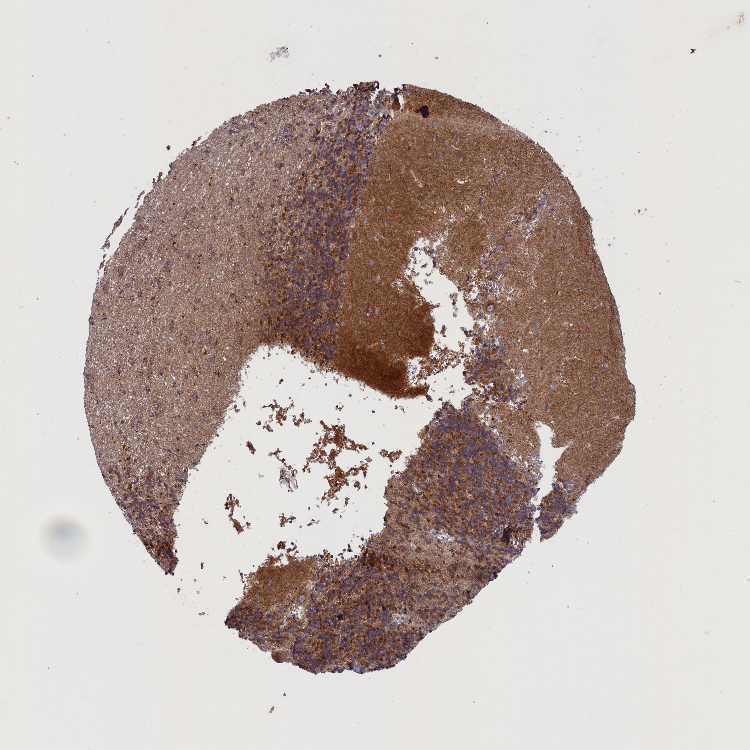

CEREBELLUM - Antibody stainingi

Antibody staining in the annotated cell types in the current human tissue is reported as not detected, low, medium, or high, based on conventional immunohistochemistry profiling in selected tissues. This score is based on the combination of the staining intensity and fraction of stained cells.

Each image is clickable and will lead to virtual microscopy that enables deeper exploration of all samples and also displays staining intensity scores, fraction scores and subcellular localization as well as patient and tissue information for each sample.

Antibody HPA043284

Purkinje cells Medium

Cells in granular layer Medium

Cells in molecular layer Not detected